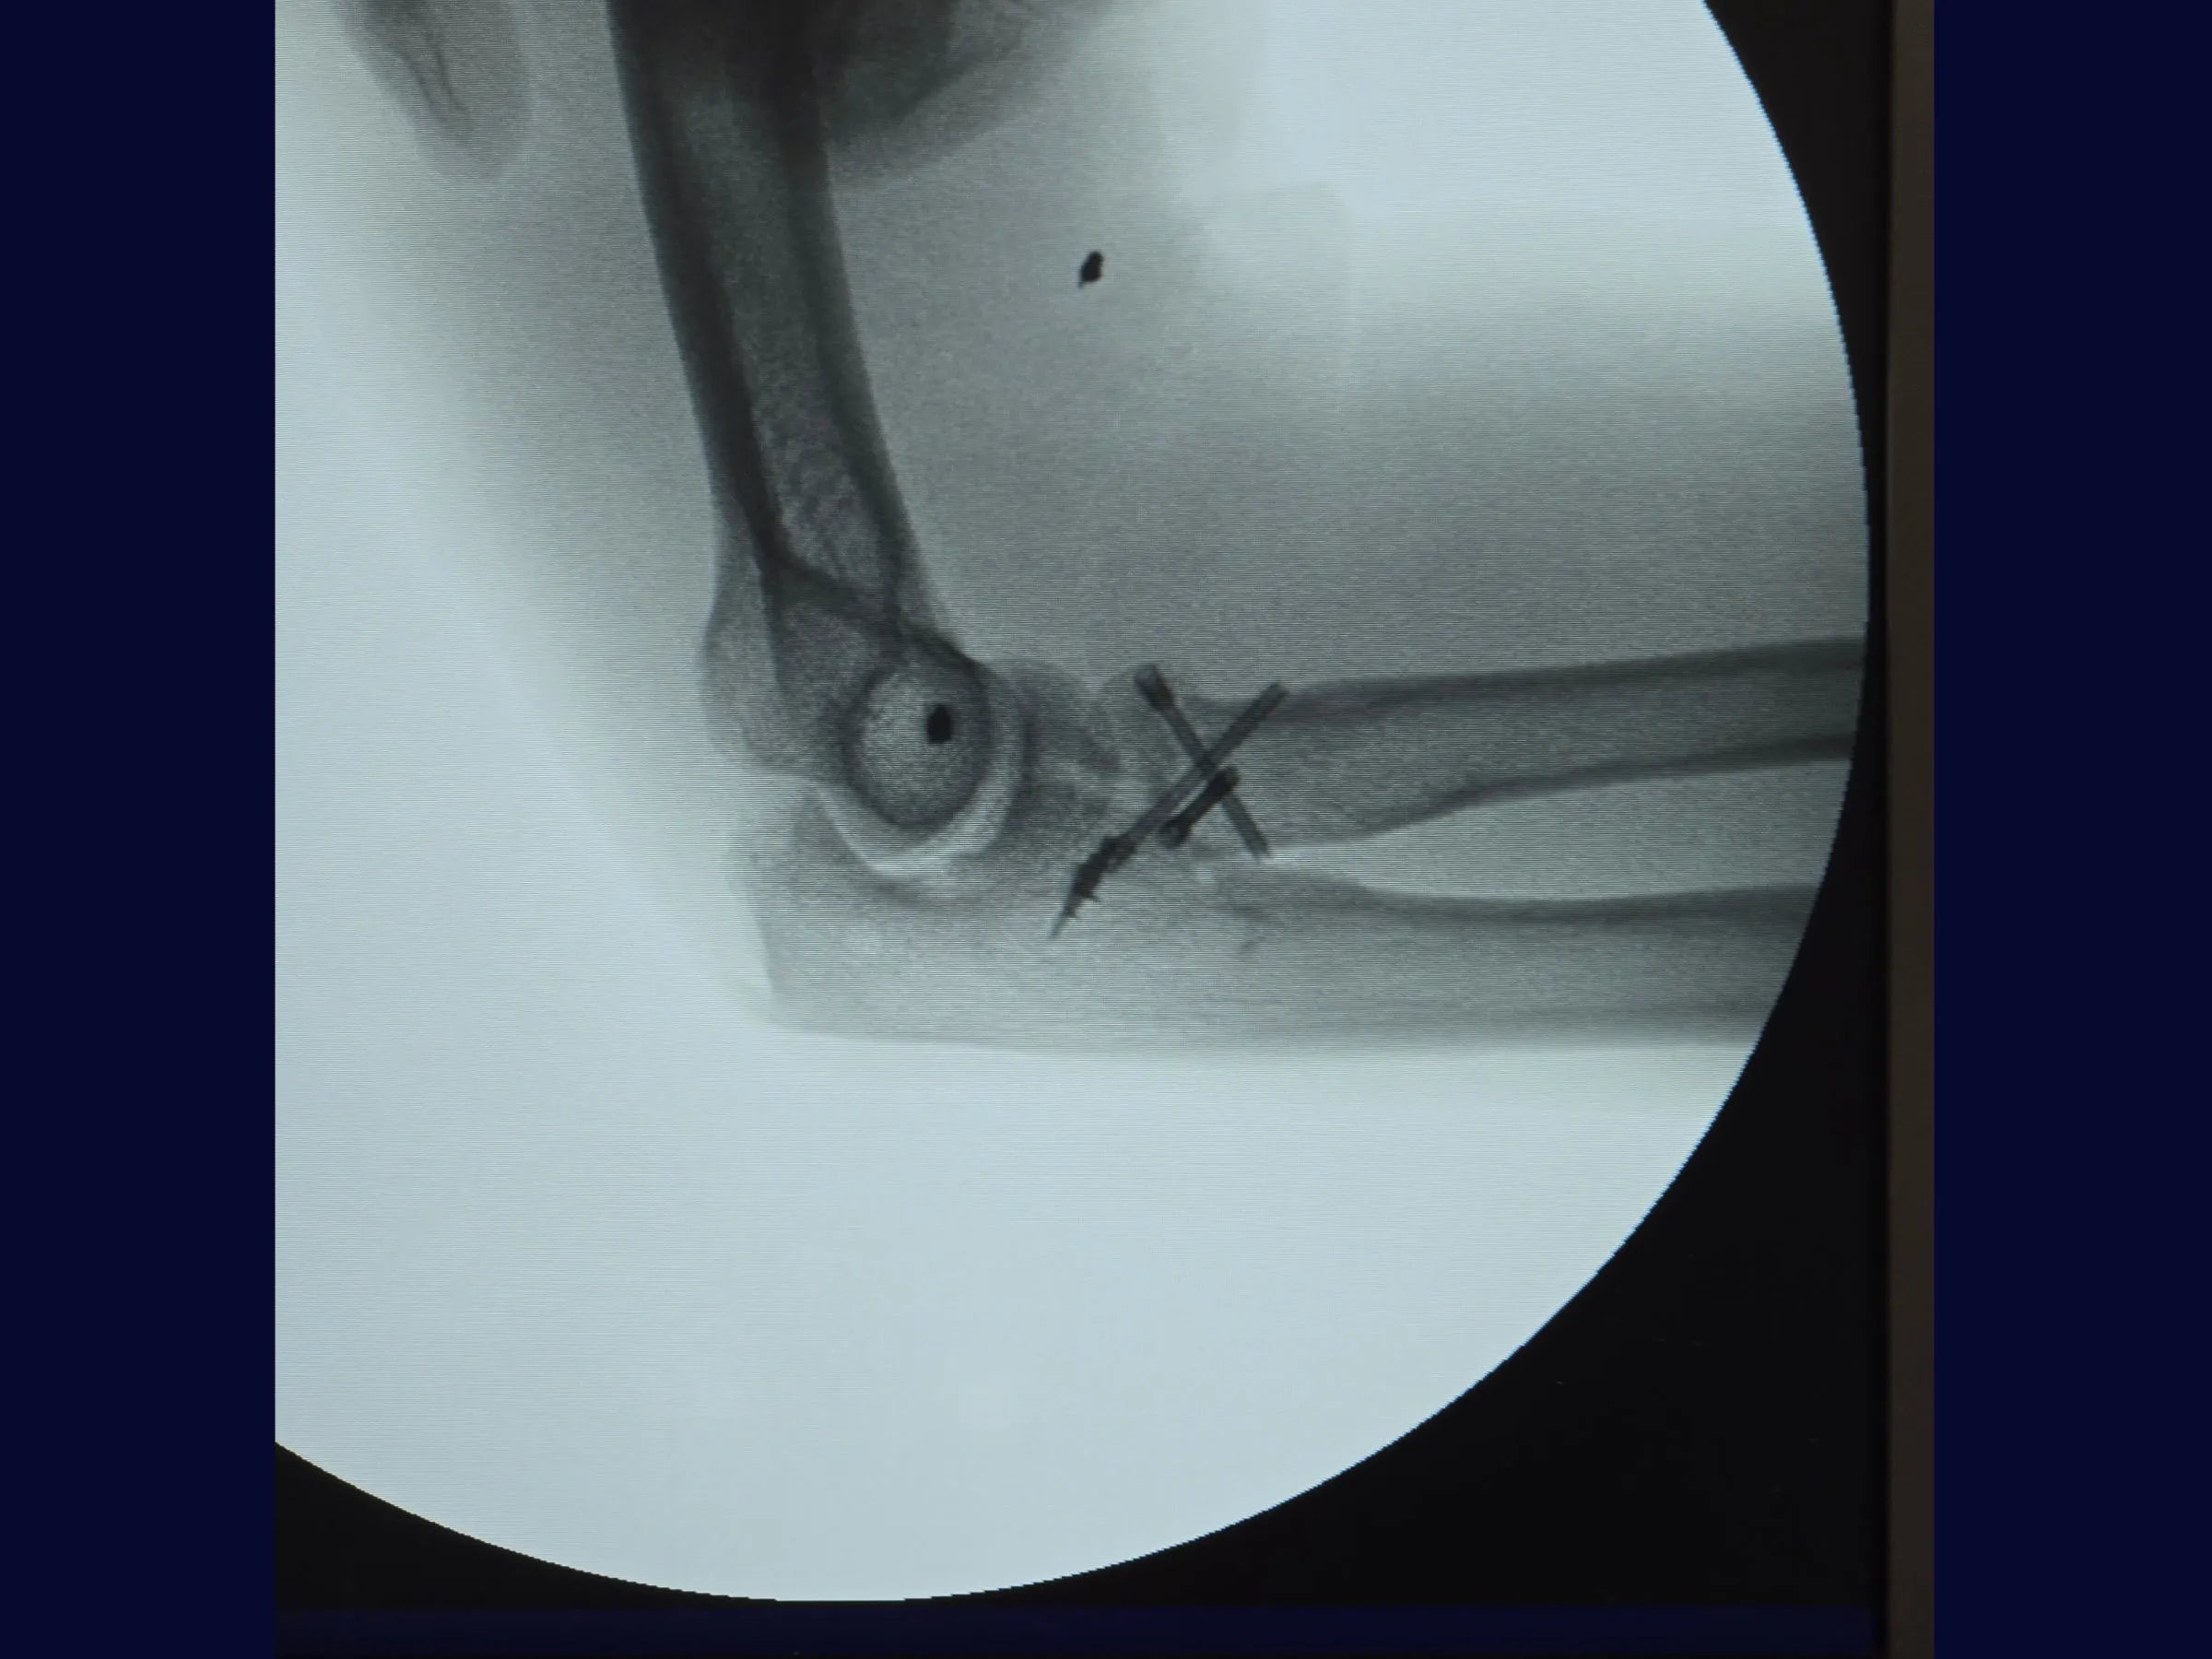

Este treinamento apresenta a técnica do tripé com parafusos de dupla compressão e reinserção capsular com âncora metálica, em vídeo 4K sob a perspectiva cirúrgica, permitindo compreender cada detalhe técnico e aplicar com segurança na prática.

- Técnica do tripé com parafusos de dupla compressão (2,4 mm).

- Fixação Segura: Parafusos sepultados em ângulo biomecânico de 45°.

- Testes de estabilidade intraoperatória e mobilidade precoce.